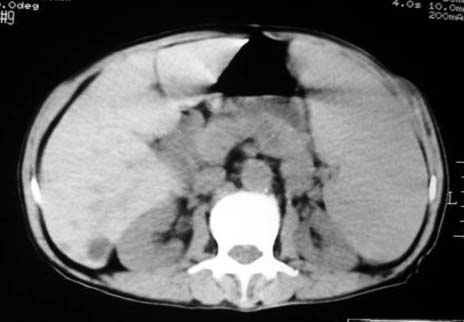

以下是引用dyqct在2007-4-20 16:38:00的发言:[br]考虑:1、巨脾;[br] 2、肝内多发低密度,首先考虑转移瘤;[br] 3、胆囊多发结石。